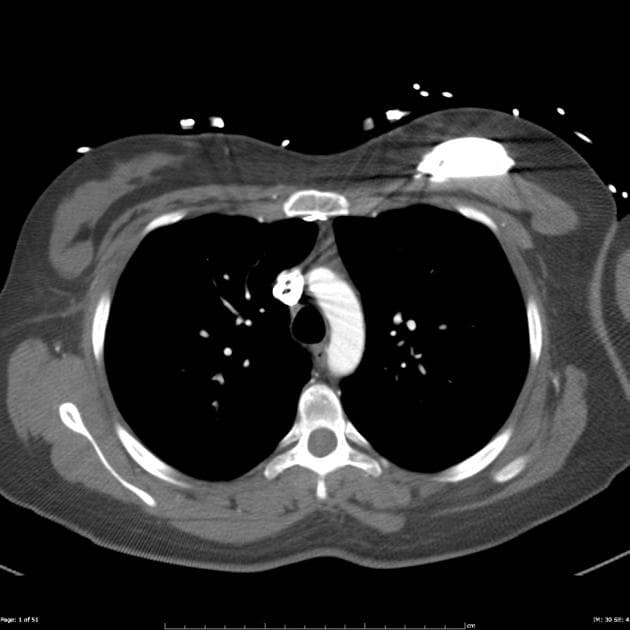

Phân tích hình thái và chức năng:

Toàn bộ co bóp cơ tim giảm, rõ rệt ở các đoạn dày lên tại vùng cơ tim đáy thành liên thất dưới và thành dưới.

Nhĩ trái tăng kích thước nhẹ. Vách liên nhĩ dày. Lỗ bầu dục còn thông (PFO).

Hở van động mạch chủ với dòng hở tâm trương tại đoạn ra thất trái (LVOT).

Không thấy hình ảnh huyết khối trong buồng tim.

Phì đại thất trái không tắc nghẽn kèm giảm nhẹ chức năng tâm thu.

Hình ảnh MRI tim phù hợp với bệnh amyloid tim (cardiac amyloidosis).